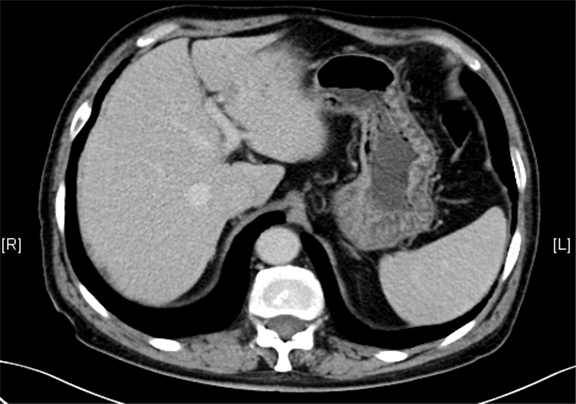

术前CT检查:

动脉期

下腹部增强CT示:肝左外叶占位,考虑恶性肿瘤伴门脉侵犯可能性大,符合肝硬化表现。

现病史:患者5月前因“肝硬化”行上腹部CT发现肝占位性病变(未见报告),建议随访观察,患者无乏力、恶心、呕吐、腹胀、腹泻、血便、食欲减退,无寒战,无头痛头晕,无皮肤粘膜黄染,无尿频、尿急、尿痛、血尿。3天前再行上腹部增强CT检查示:肝左外叶占位,考虑恶性肿瘤伴门脉侵犯可能性大,建议MR平扫+强化符合肝硬化表现。双肾多发小囊肿可能性大